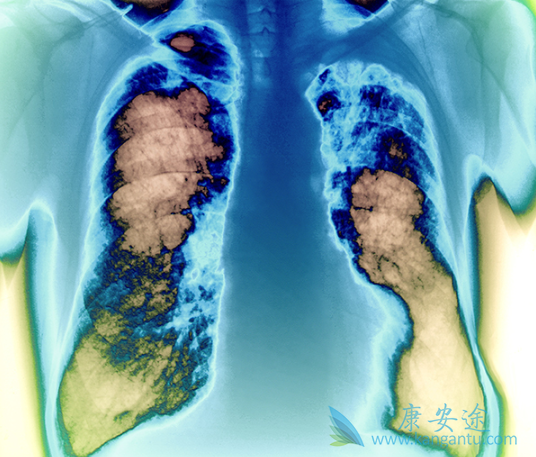

间皮瘤作为一种隐匿性肿瘤,可发于胸膜腔、腹膜腔、睾丸鞘膜或心包的间皮表面,其中大部分病例源于胸膜。恶性胸膜间皮瘤(MPM)是最常见的恶性间皮瘤,绝大多数MPM患者发病年龄在60岁及以上,石棉暴露是发生胸膜间皮瘤最重要的危险因素。大部分患者因逐渐出现非特异性症状而就诊,如胸痛、呼吸困难、咳嗽、声音嘶哑、盗汗或吞咽困难等。正因为MPM的临床表现没有特异性而且隐匿,许多患者在就诊时已偏晚期,使得治疗比较棘手。对于怀疑MPM的患者首选胸部增强CT检查,以确定胸膜异常和病变程度,如果存在胸腔积液,可以进行胸水细胞学病理诊断或胸膜活检。

但这种方法可能不能提供足够的组织以明确MPM的诊断,或者说不能很好地鉴别MPM与腺癌等。在这种情况下,可通过电视胸腔镜手术活检或开胸手术进行外科干预,既可以直观胸膜病变范围,又可获得足够标本,有利于诊断和分期。此外,我们在手术同时可以行支气管镜检查进行评估,因为间皮瘤中通常不合并支气管内病变,如果存在支气管内病变则提示间皮瘤的诊断需要慎重。MPM患者的预后很差,患者的中位生存期为6-18个月,5年生存率不足10%,极少患者可能治愈。大部分受累患者最终因局部扩散和呼吸衰竭死亡。

其中,分期、组织学类型及手术切除的彻底性是最主要的预后因素,肉瘤样和混合型组织学亚型的预后比上皮样间皮瘤差,纯上皮样变异型的预后最佳。目前MPM尚无成熟的综合治疗模式,手术主要适用于全身条件良好,无纵隔淋巴结转移的早期患者,上皮型更适合;手术方式主要包括扩大胸膜肺切除术和胸膜剥脱术;一线化疗方案是顺铂或卡铂联合培美曲塞,但有效率仍不高;放疗受限于肿瘤体积过于广泛,难以达到根治量。